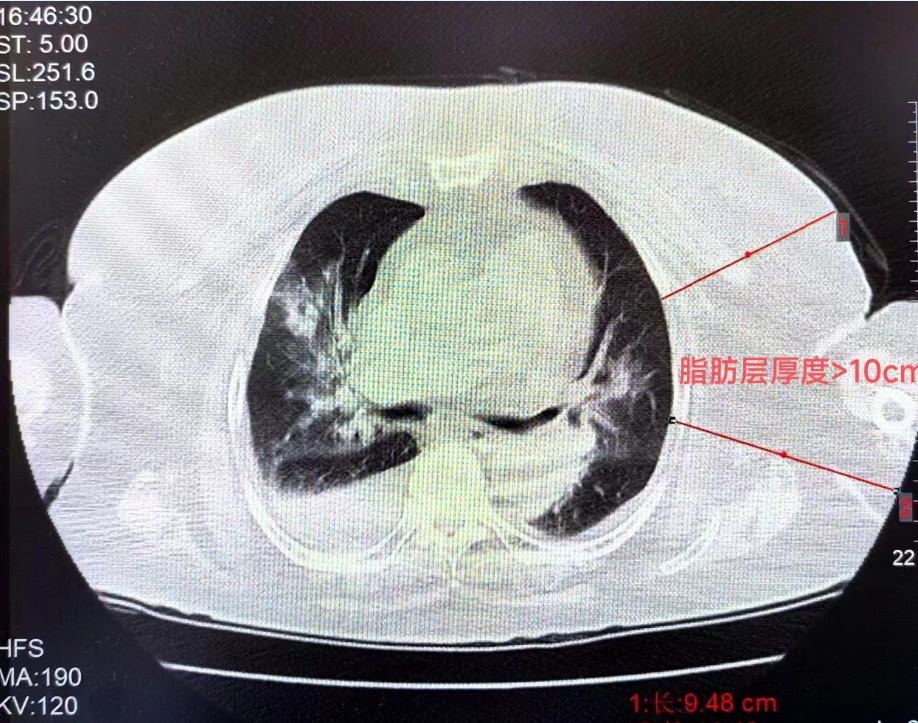

王女士(化名)身高156.5cm,体重90kg,BMI(体重指数)36.7kg/㎡(BMI正常范围是18.5~23.9),腰围116cm,臀围121cm,一晚上睡眠395分钟中,呼吸暂停了427次,单次最长憋气时间74秒,AHI指数(呼吸暂停、低通气指数)高达71.8。

福建省人民医院呼吸科副主任医师林劲榕表示,这是2月初医院心内科请他会诊的病人。林劲榕刚见到王女士时,她清醒时的二氧化碳最高达到116mmHg,属于极重度二氧化碳潴留,正常值应在35-45mmHg,患者最低血氧48%,提示极重度低血氧,合并严重心肺功能不全。

通过睡眠监测、肺功能等检查,结合病情等,医生们得出结论——原来,缺氧和超高二氧化碳分压竟是肥胖惹的祸——王女士确诊为肥胖低通气综合征。